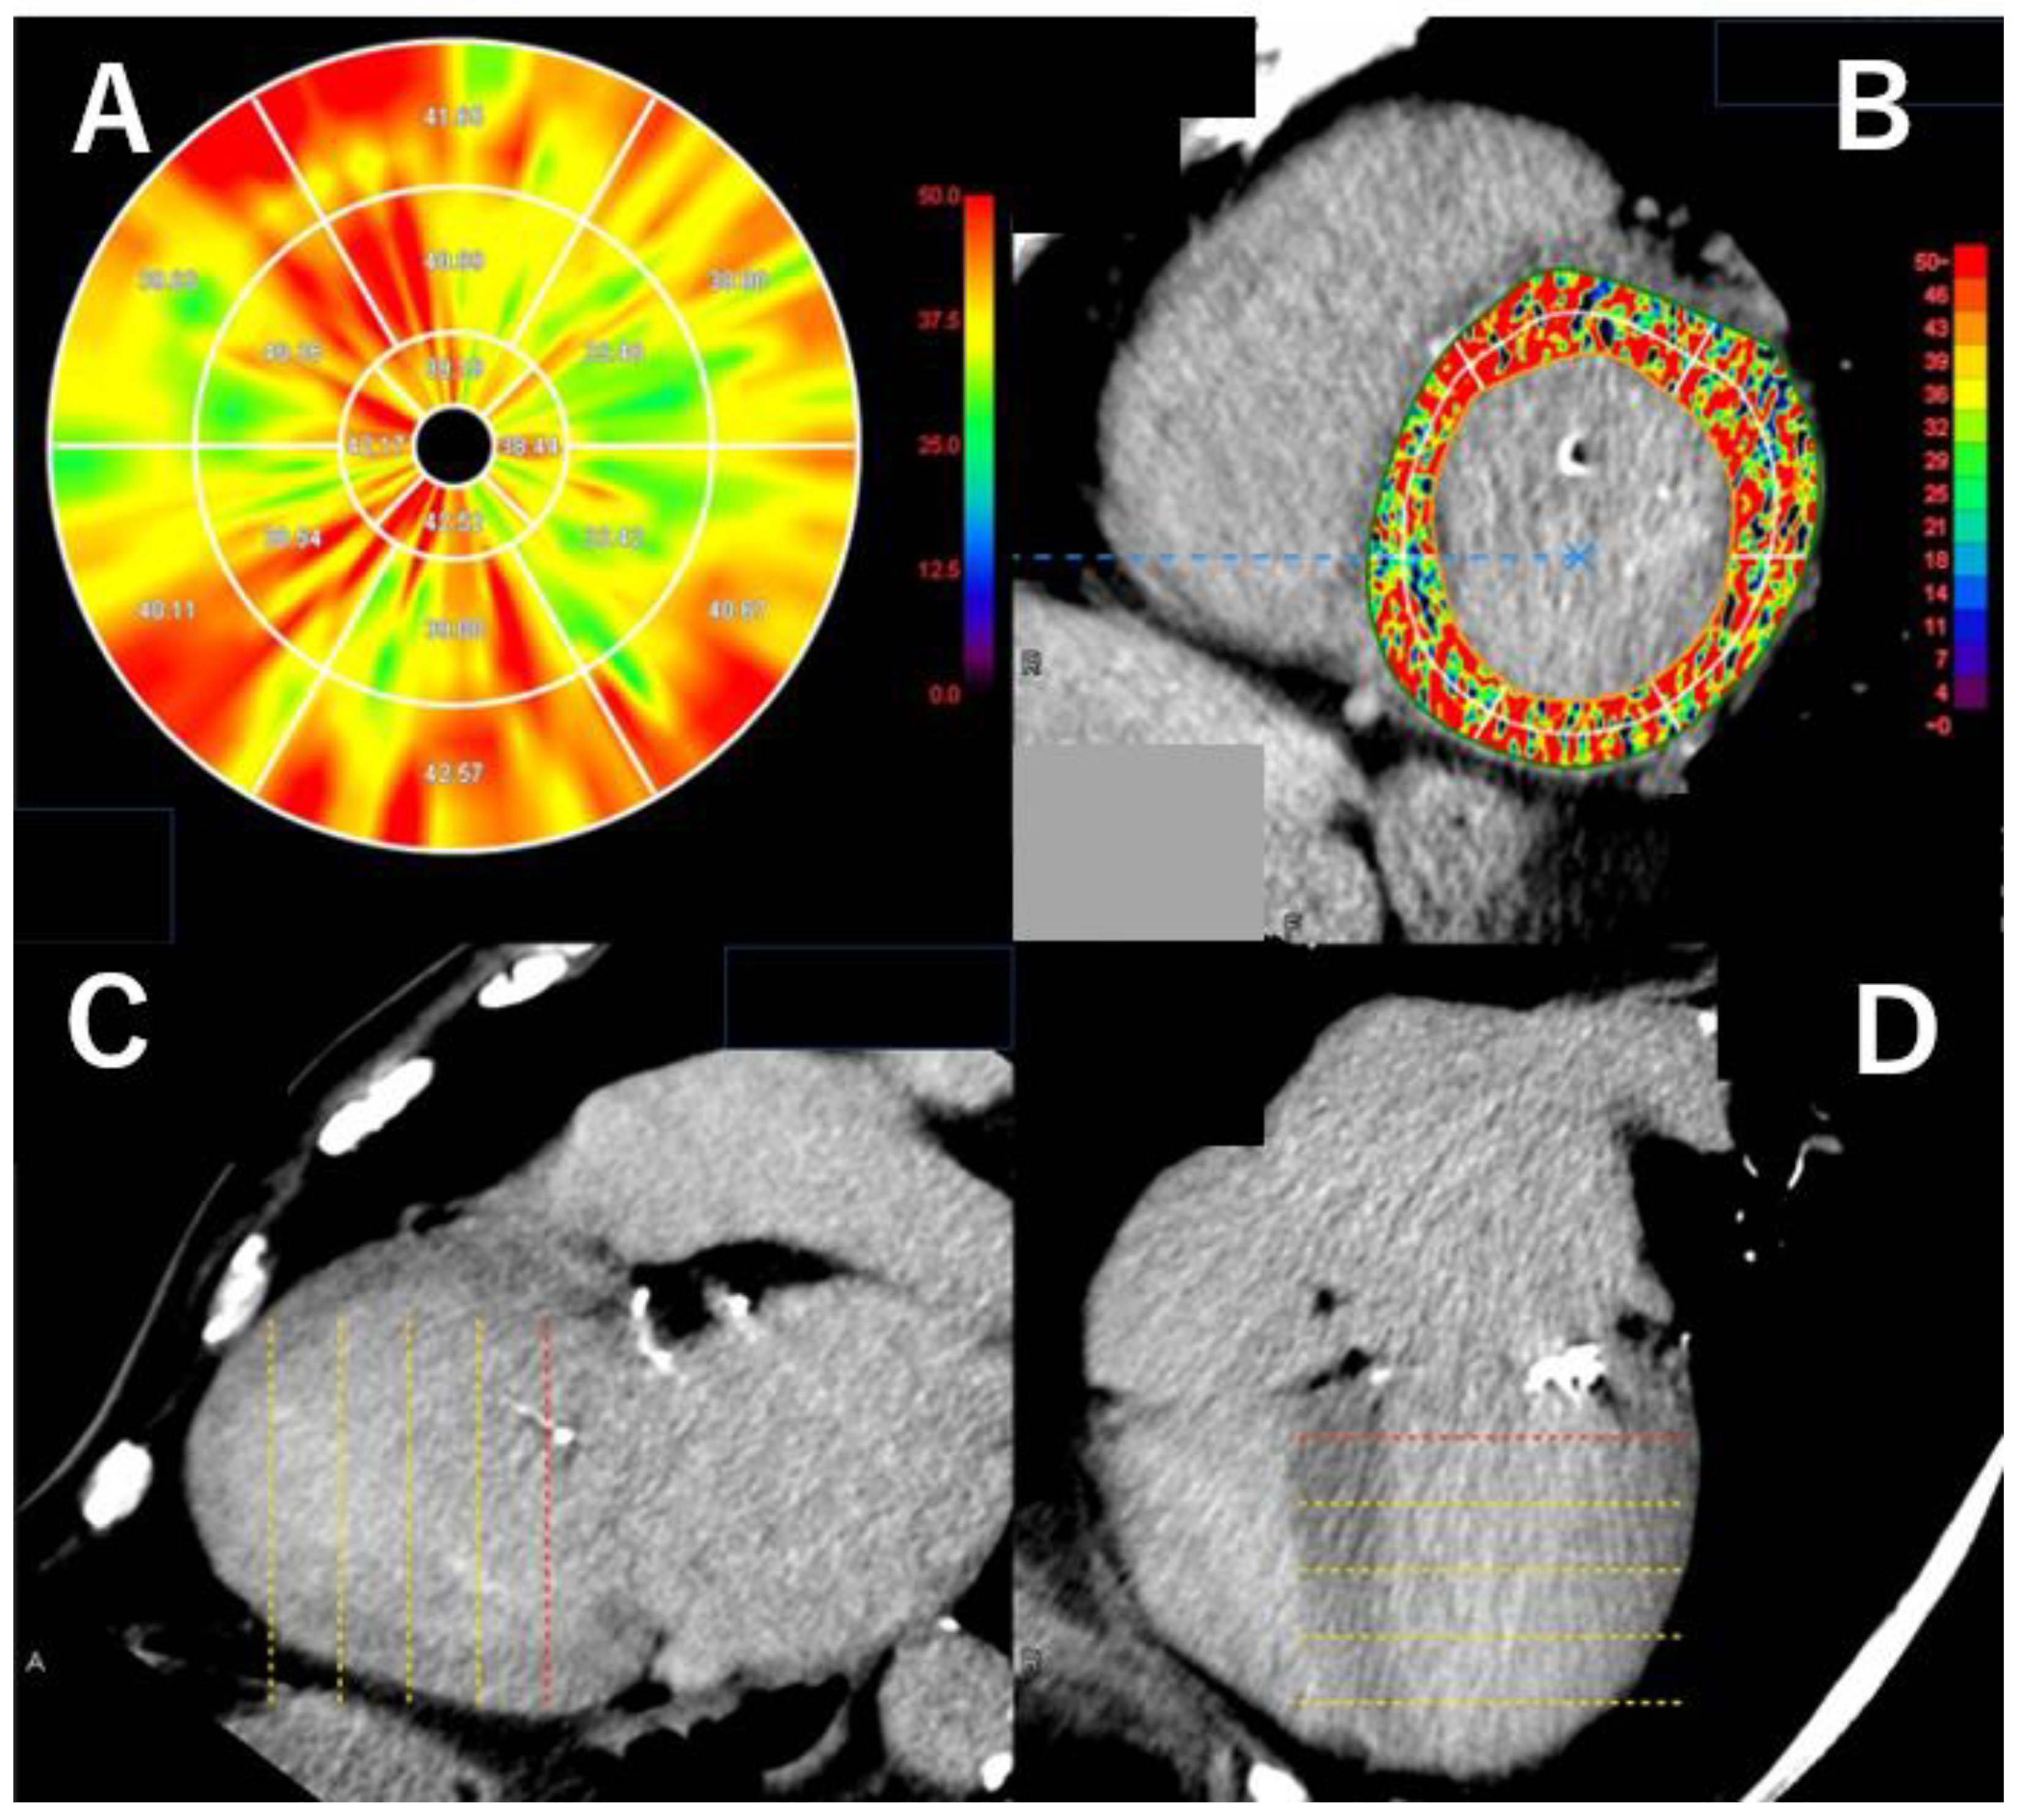

3.5. The Analysis of Myocardial Damage on Computed Tomography

3.6. Myocardial Strain Analysis on Computed Tomography